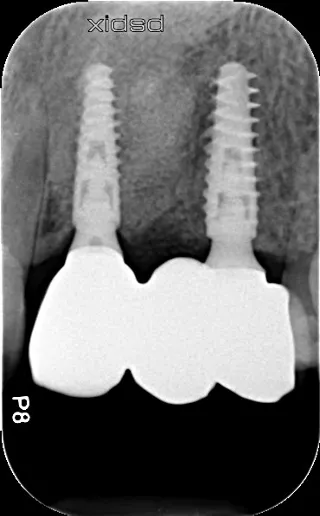

17a-b-c-d. Retro-alveolar X-rays at the end of treatment. Note bone behavior around the 4 implant collars. Soft tissue height above each collar was 3 to 4 mm.